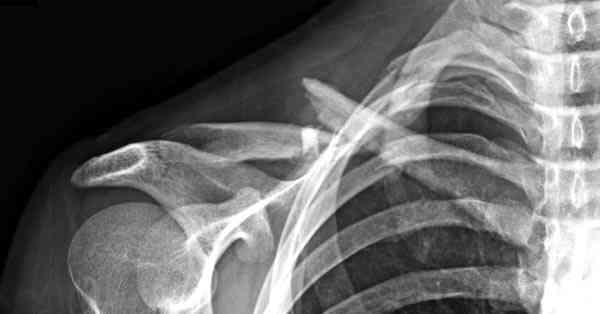

Тактика лечения переломов ключицы у нас не отличается от тактики, упомянутой коллегами - при изолированных переломах в основном придерживаемся консервативной тактики.

Недавно разбирали случай ложного сустава.

45 летная женщина после автоаварии, алкоголь 163 и 20 летним стажем курения.

Консервативное лечение, через 8 мес. операция Rockwood pin с костной пластикой в нашем городе другим врачом. После 8 недели падение, гвоздь удален оперирующим хирургом, больная направлена к нам. Фиксация реконструктивной пластиной с трикортикальным графтом, добавлен BMP-2. Для стабилизации фиксацию провели через акромион.

Вот уже два месяца больная также продолжает жаловаться на боли, буквально на днях удалили акромиальную часть пластины с специальной пилой с алмазным покрытием для медицинского металла. До сих пор судьба ложного сустава неизвестна....